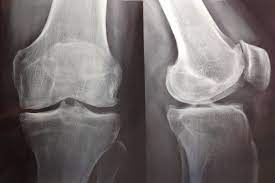

Restauración del ensayo PRGF: un ensayo clínico aleatorizado en plasma rico en factores de crecimiento para la artrosis de rodilla

este nuevo análisis del estudio PRGF no encontró ningún beneficio clínica o estadísticamente significativo del plasma rico en factores de crecimiento (PRGF) en comparación con el ácido hialurónico. La restauración del Estudio PRGF muestra la urgencia de cambios importantes en las prácticas de supervisión e informes de juicios. En el futuro, se necesita acceso oportuno a todos los documentos de ensayos clínicos para minimizar el riesgo de sesgo de informe. Del mismo modo, los comités de ética deben estar listos para intervenir cada vez que surja un caso de posible mala conducta. Trials, 18 de enero de 2023